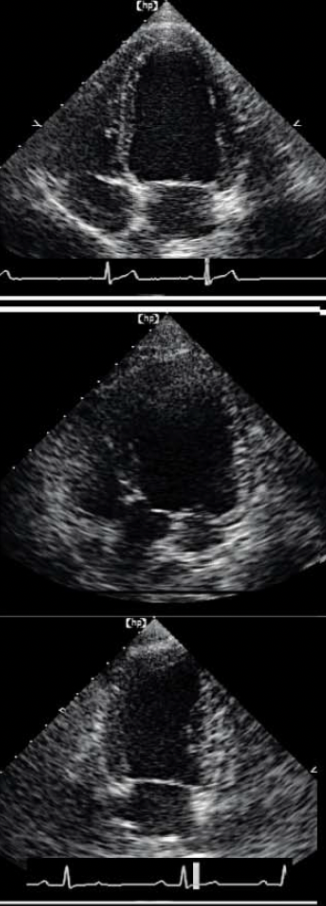

Name the ECHO VIEW and STRUCTURES

LEFT APICAL VIEWS